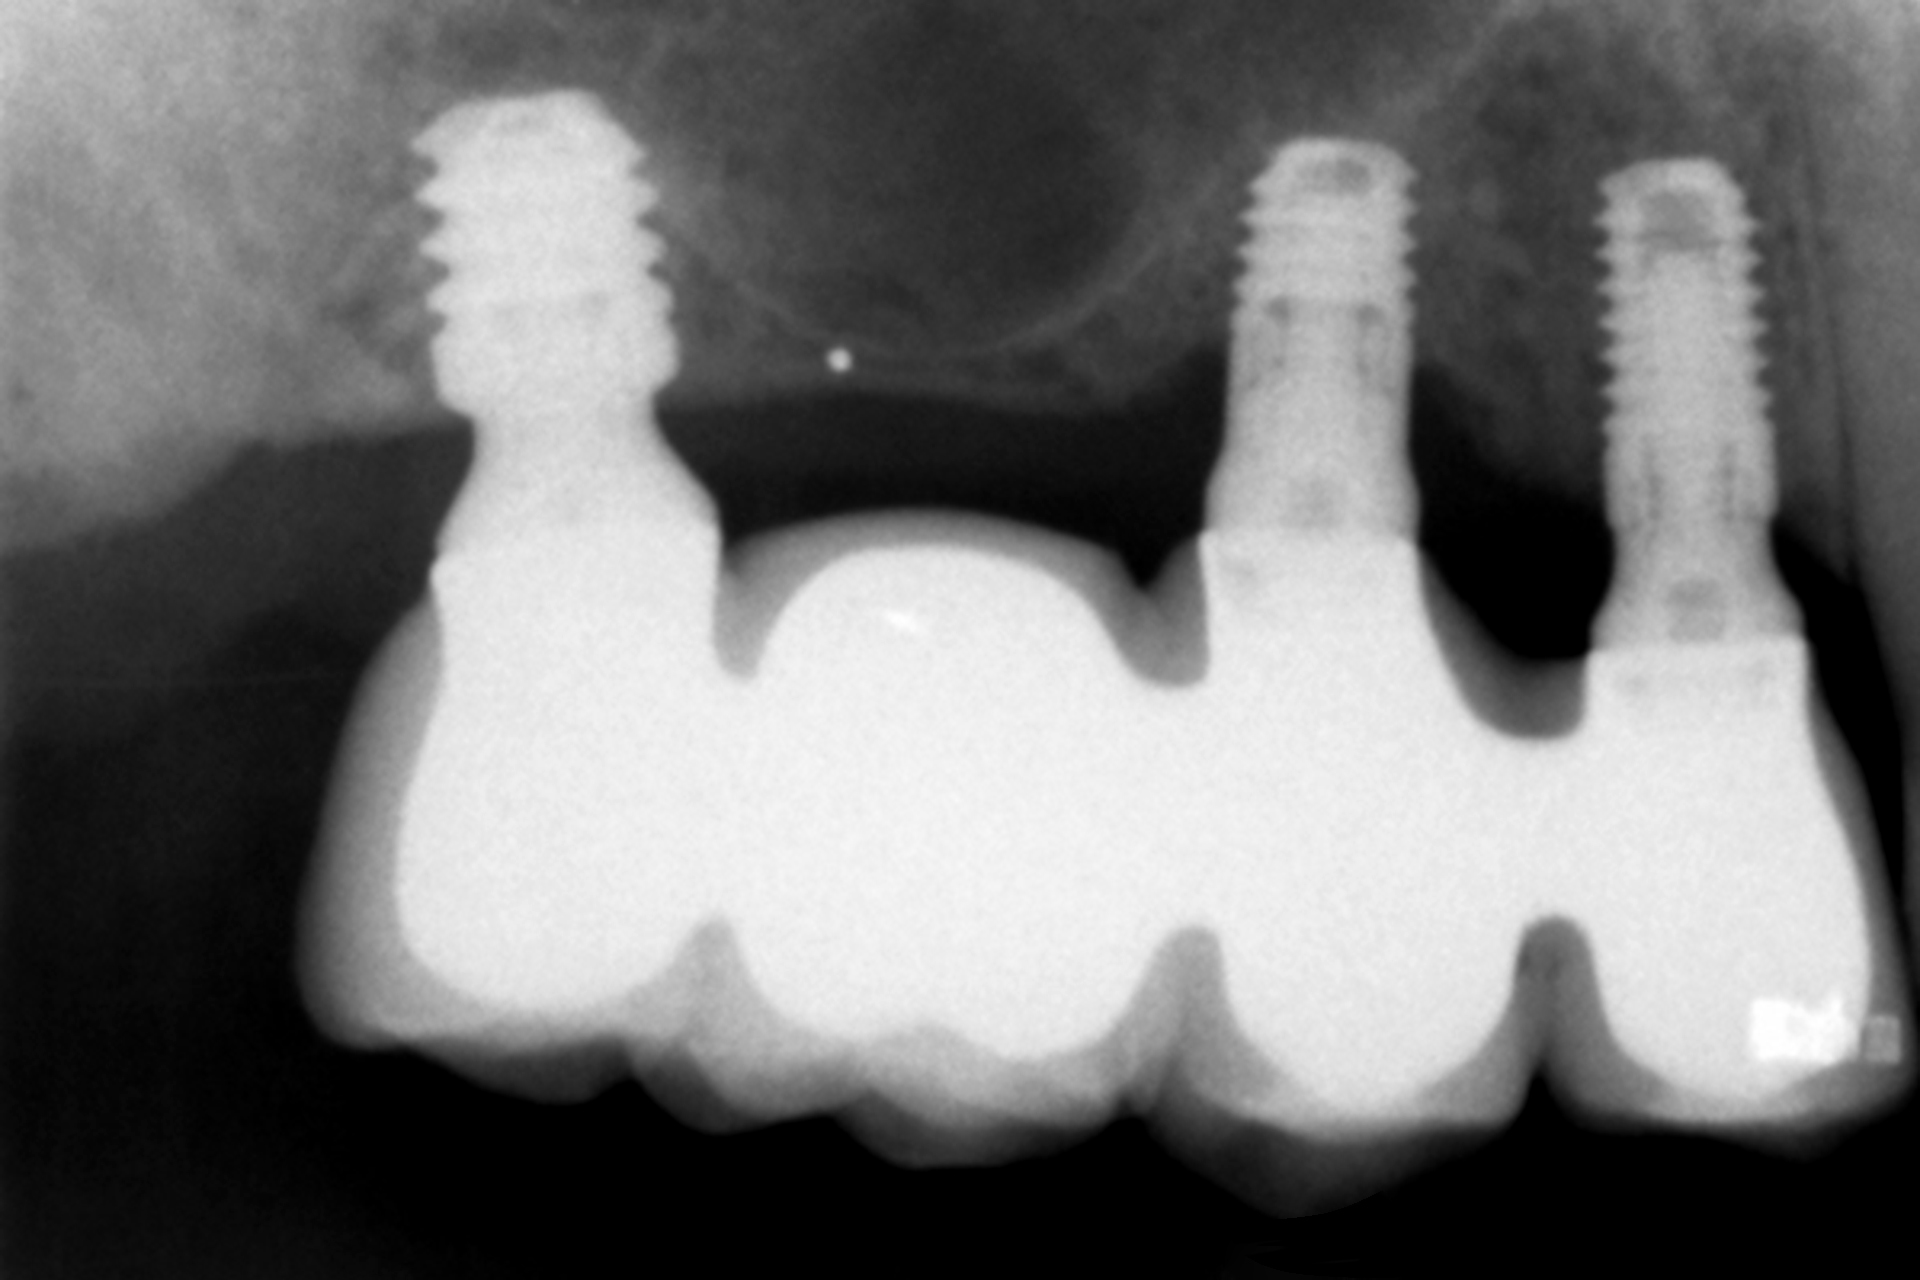

Tutti gli impianti sono stati caricati entro 24 ore dall’inserimento mediante protesi provvisorie in resina a carico immediato, realizzate con strutture a barra articolata. L’analisi dei diversi tipi di protesi ferulizzate ha evidenziato una predominanza delle riabilitazioni parziali. Il gruppo più numeroso era costituito dalle protesi supportate da due impianti e due elementi dentari, pari al 33,3% dei casi, seguito dalle protesi complete, presenti nel 19,4% dei pazienti. Altri disegni protesici sono stati utilizzati con frequenze comprese tra l’8,3% e il 16,7%, riflettendo l’adattamento del piano terapeutico alle specifiche condizioni anatomiche di ciascun paziente, mantenendo in tutti i casi la ferulizzazione rigida degli impianti come principio biomeccanico fondamentale (Figura 1).

In 19 impianti sono state eseguite procedure complementari contestualmente all’inserimento implantare: in due casi rigenerazione verticale con osso autologo da fresaggio associato a PRGF-Endoret; in 11 casi rialzo del seno mascellare transalveolare con osso autologo e PRGF-Endoret; in sei casi sovracorrezione vestibolare mediante osso autologo e PRGF-Endoret, associando uno strato di biomateriale (idrossiapatite bovina) per ridurre il riassorbimento volumetrico. Quattro impianti da 4,5 mm sono stati ferulizzati ad altri impianti della stessa lunghezza, per un totale di otto impianti ultra-corti ferulizzati tra loro, configurando ponti supportati da tre impianti. La protesizzazione definitiva è stata eseguita tra tre e nove mesi dopo il carico immediato. Le protesi definitive erano in metallo-ceramica nell’80,6% dei casi e in resina con struttura metallica nei restanti.

Al termine del follow-up, la perdita ossea crestale media è stata di 0,73 ± 0,18 mm in mesiale e di 0,85 ± 0,34 mm in distale. Alcuni casi clinici rappresentativi sono illustrati nelle Figure 2-10.